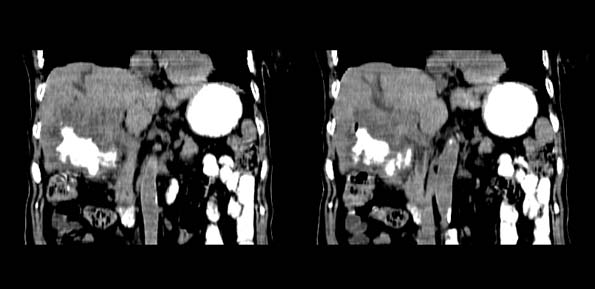

以下是引用bailaode在2008-6-12 22:10:00的发言:[br]资料中未提及患者有无急腹症体征,这个很重要。[br] ct表现:肝内境界模糊之低密度灶,内有含对比剂之液气平面.(提示肝内病灶与胃肠道沟通) [br] 1、根据“长城干红 ”所提供的资料“患者,女,74岁,黑便月余,消瘦,一般状况差,白细胞1万四千”,是否可认为是个慢性病程?那么我首先考虑:十二指肠结核,十二指肠--胆管瘘,继发胆道逆行感染肝脓肿形成。[br] 2、如有急腹症体征则考虑:十二指肠溃疡穿孔?十二指肠占位伴穿孔?

以下是引用拾荒者在2008-6-13 22:13:00的发言:[br]病灶与升结肠、肝脏及十二指肠关系密切,且结肠降段见造影剂影,支持结肠与十二指肠瘘形成,原因及原发病在哪不好定,不过,虽说有风险,但还是应该手术治疗,单纯抗感染估计不行。